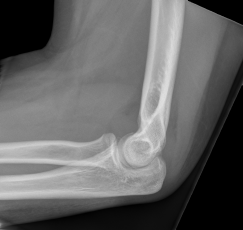

Warsztaty z rehabilitantem

Warsztaty składają się z 3 części:

pogadanka o przyczynach niesprawności oraz sposobach ich usuwania

odpowiedzi na pytania

indywidualne konsultacje

Po warsztatach można umówić się na osobiste porady i zabiegi.